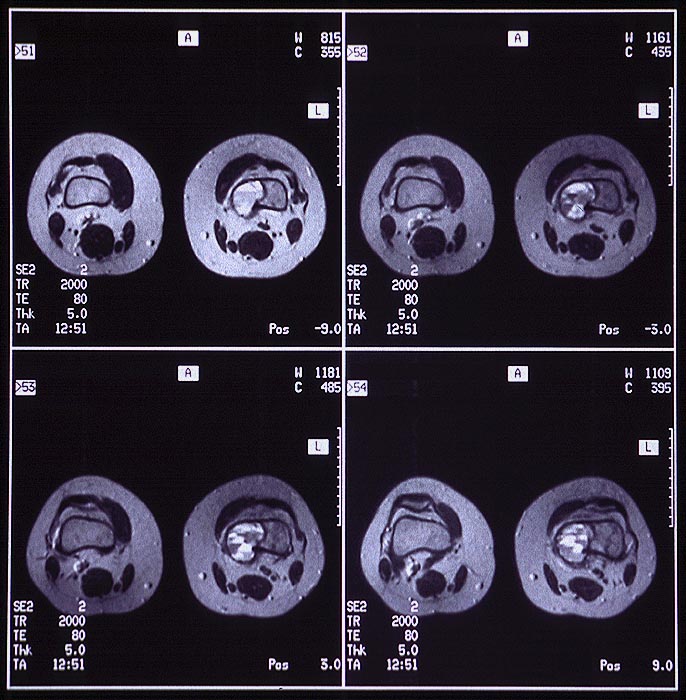

PathoPic – image database / PathoPic ID 5035 - Aneurysmatische Knochenzyste

Aneurysmatische Knochenzyste

benigner Tumor

Knochen, Femur

Bilder Typ